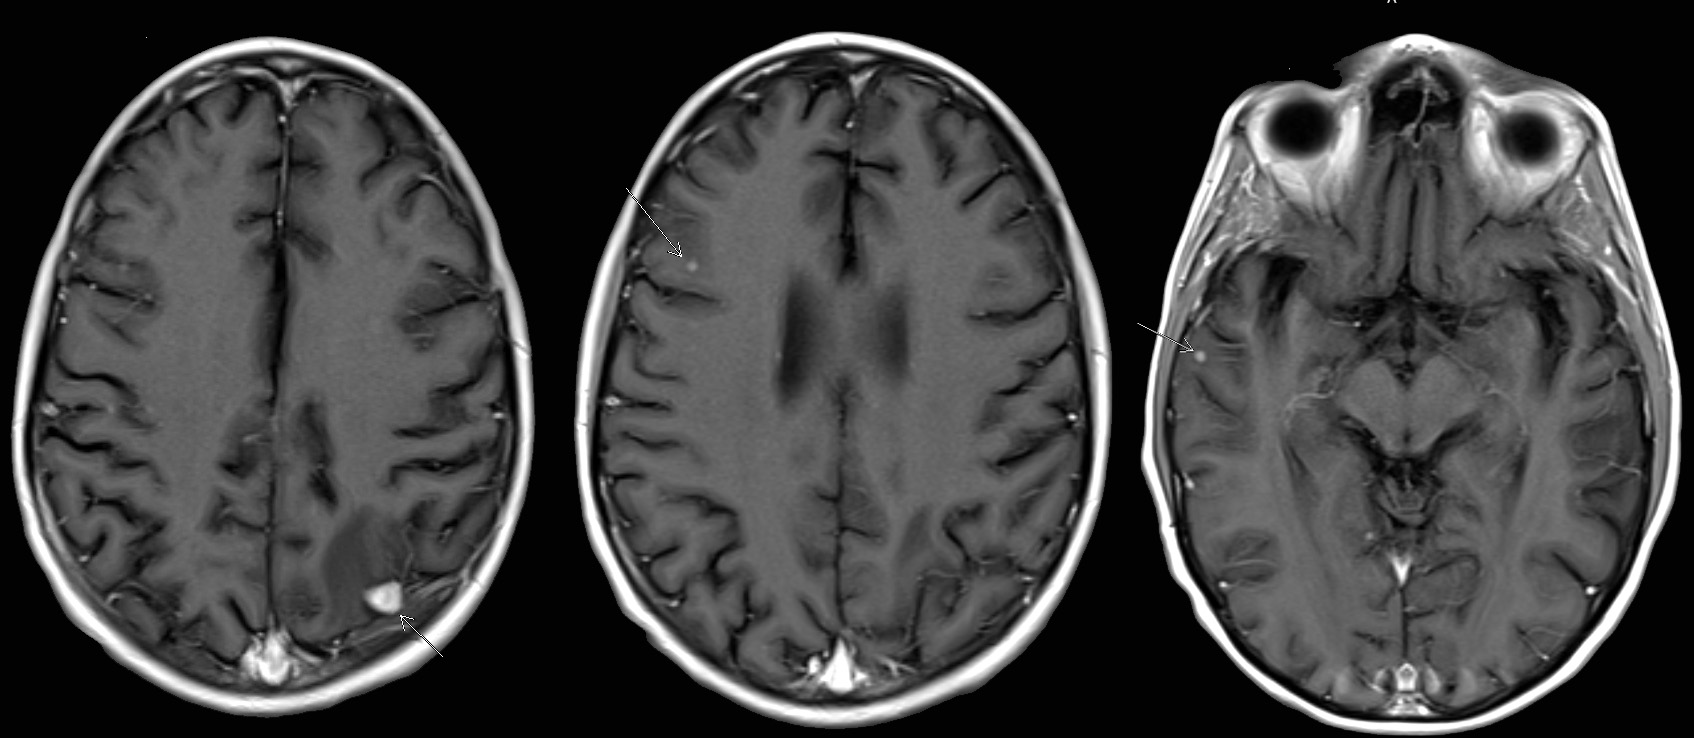

Radiology images

Contributed by Chunyu Cai, M.D., Ph.D. (Case #532)

- 35 year old HIV+ man with diffuse lymphadenopathy (Case of the Week #218)

- 52 year old man with a history of HIV infection and Kaposi sarcoma 5 years prior, presented with lower extremity weakness (Case of the month #532)

Microscopic (histologic) description

- Nodes show partial / complete effacement by storiform pattern of bland spindle cells, some with vacuoles

- Numerous vessels lined by plump endothelial cells, plasma cells and lymphocytes

- No multinucleated tumor cells, no foamy histiocytes